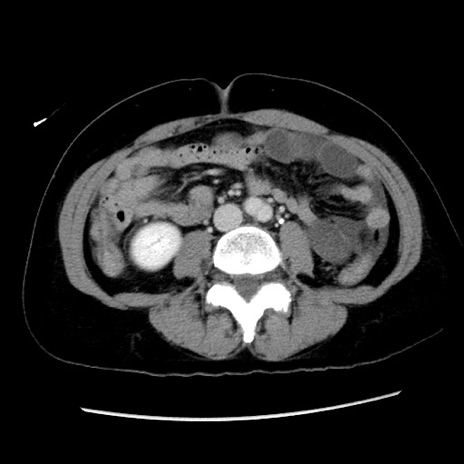

冠状断像

症例10(横断像)

【症例】 50歳代女性

【主訴】 腹痛

【現病歴】前日生レバーを食べた。今朝に排便あり。 昼前に突然発症の腹痛を生じ、当院救急外来を受診した。

【既往歴】 子宮筋腫にてで子宮全摘後

【身体所見】 意識清明、腹部:平坦、軟、下腹部やや左を中心に圧痛・反跳痛あり、筋性防御あり

【データ】WBC 7800、CRP 0.07